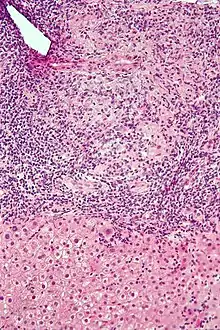

| Micrograph of PBC showing bile duct inflammation and injury, H&E stain | |

Intermediate-magnification micrograph of PBC showing bile duct inflammation and periductal granulomas, liver biopsy, H&E stain

On microscopic examination of liver biopsy specimens, PBC is characterized by chronic, nonsuppurative inflammation, which surrounds and destroys interlobular and septal bile ducts. These histopathologic findings in primary biliary cholangitis include:[32]

- Inflammation of the bile ducts, characterized by intraepithelial lymphocytes

- Periductal epithelioid granulomas.

- Proliferation of bile ductules

- Fibrosis (scarring)

The Ludwig and Scheuer scoring systems have historically been used to stratify four stages of PBC, with stage 4 indicating the presence of cirrhosis. In the new system of Nakanuma, the stage of disease is based on fibrosis, bile duct loss, and features of cholestasis, i.e. deposition of orcein-positive granules, whereas the grade of necroinflammatory activity is based on cholangitis and interface hepatitis. The accumulation of orcein-positive granules occurs evenly across the PBC liver, which means that staging using the Nakanuma system is more reliable regarding sampling variability.